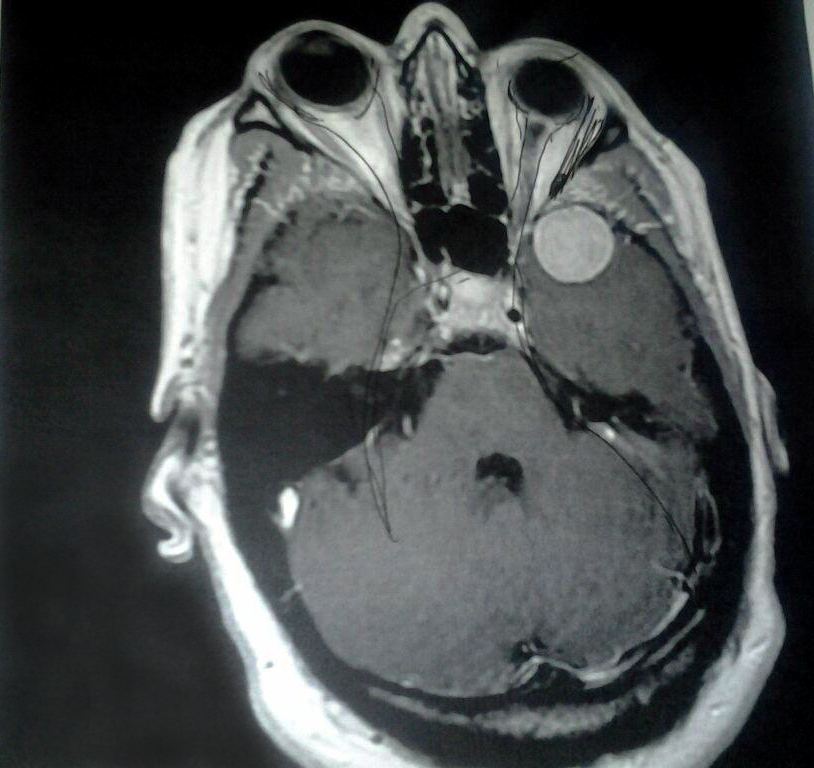

13 Types of Brain Tumors [SCIENTIFIC IMAGES] Left Side Pains Sharp Eye Pain Brain Tumor Blurred, double or even loss of vision can be signs of a brain tumor. What part of the brain the. Brain tumor symptoms can vary from person to person and depending on where the tumor is in the brain. Here, we discuss 6 signs and symptoms of a brain tumor. Learn about numbness, headaches and other signs that you may. Sharp Eye Pain Brain Tumor.

Benign brain tumour, CT scan Stock Image F011/7580 Science Photo Sharp Eye Pain Brain Tumor Any type of brain tumor has the potential to cause vision problems if it puts pressure on the optic nerve or otherwise affects the eyes or vision processing. Learn about numbness, headaches and other signs that you may have a brain tumor. Losing strength or weakness in an arm or leg may be a brain tumor symptom. Blurred, double or. Sharp Eye Pain Brain Tumor.